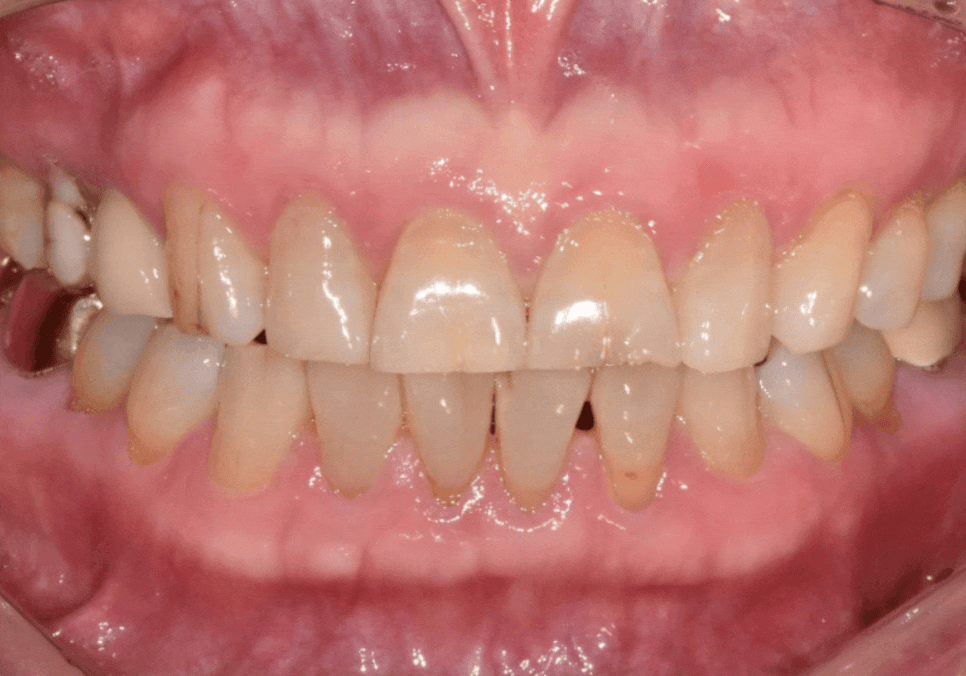

4개월 뒤,, 환자분께서 다시 내원하셨는데요.

식사 도중 앞니 하나(#11)가 부러져 오셨어요.

안타깝게도 뿌리만 남아

임플란트가 필요했습니다.

안타까운 상황이었지만,

다행히 하나씩 따로 씌워둔 덕분에

수습 과정은 훨씬 수월했습니다.^^

만약 6개를 하나로 묶어두었더라면

어땠을까요?

이 치아 하나 때문에 멀쩡한 나머지 5개까지

전부 뜯어내는 큰 공사가 됐을 텐데,

부러진 곳만 따로 수습하며

수월하게 치료를 마무리할 수 있었습니다.